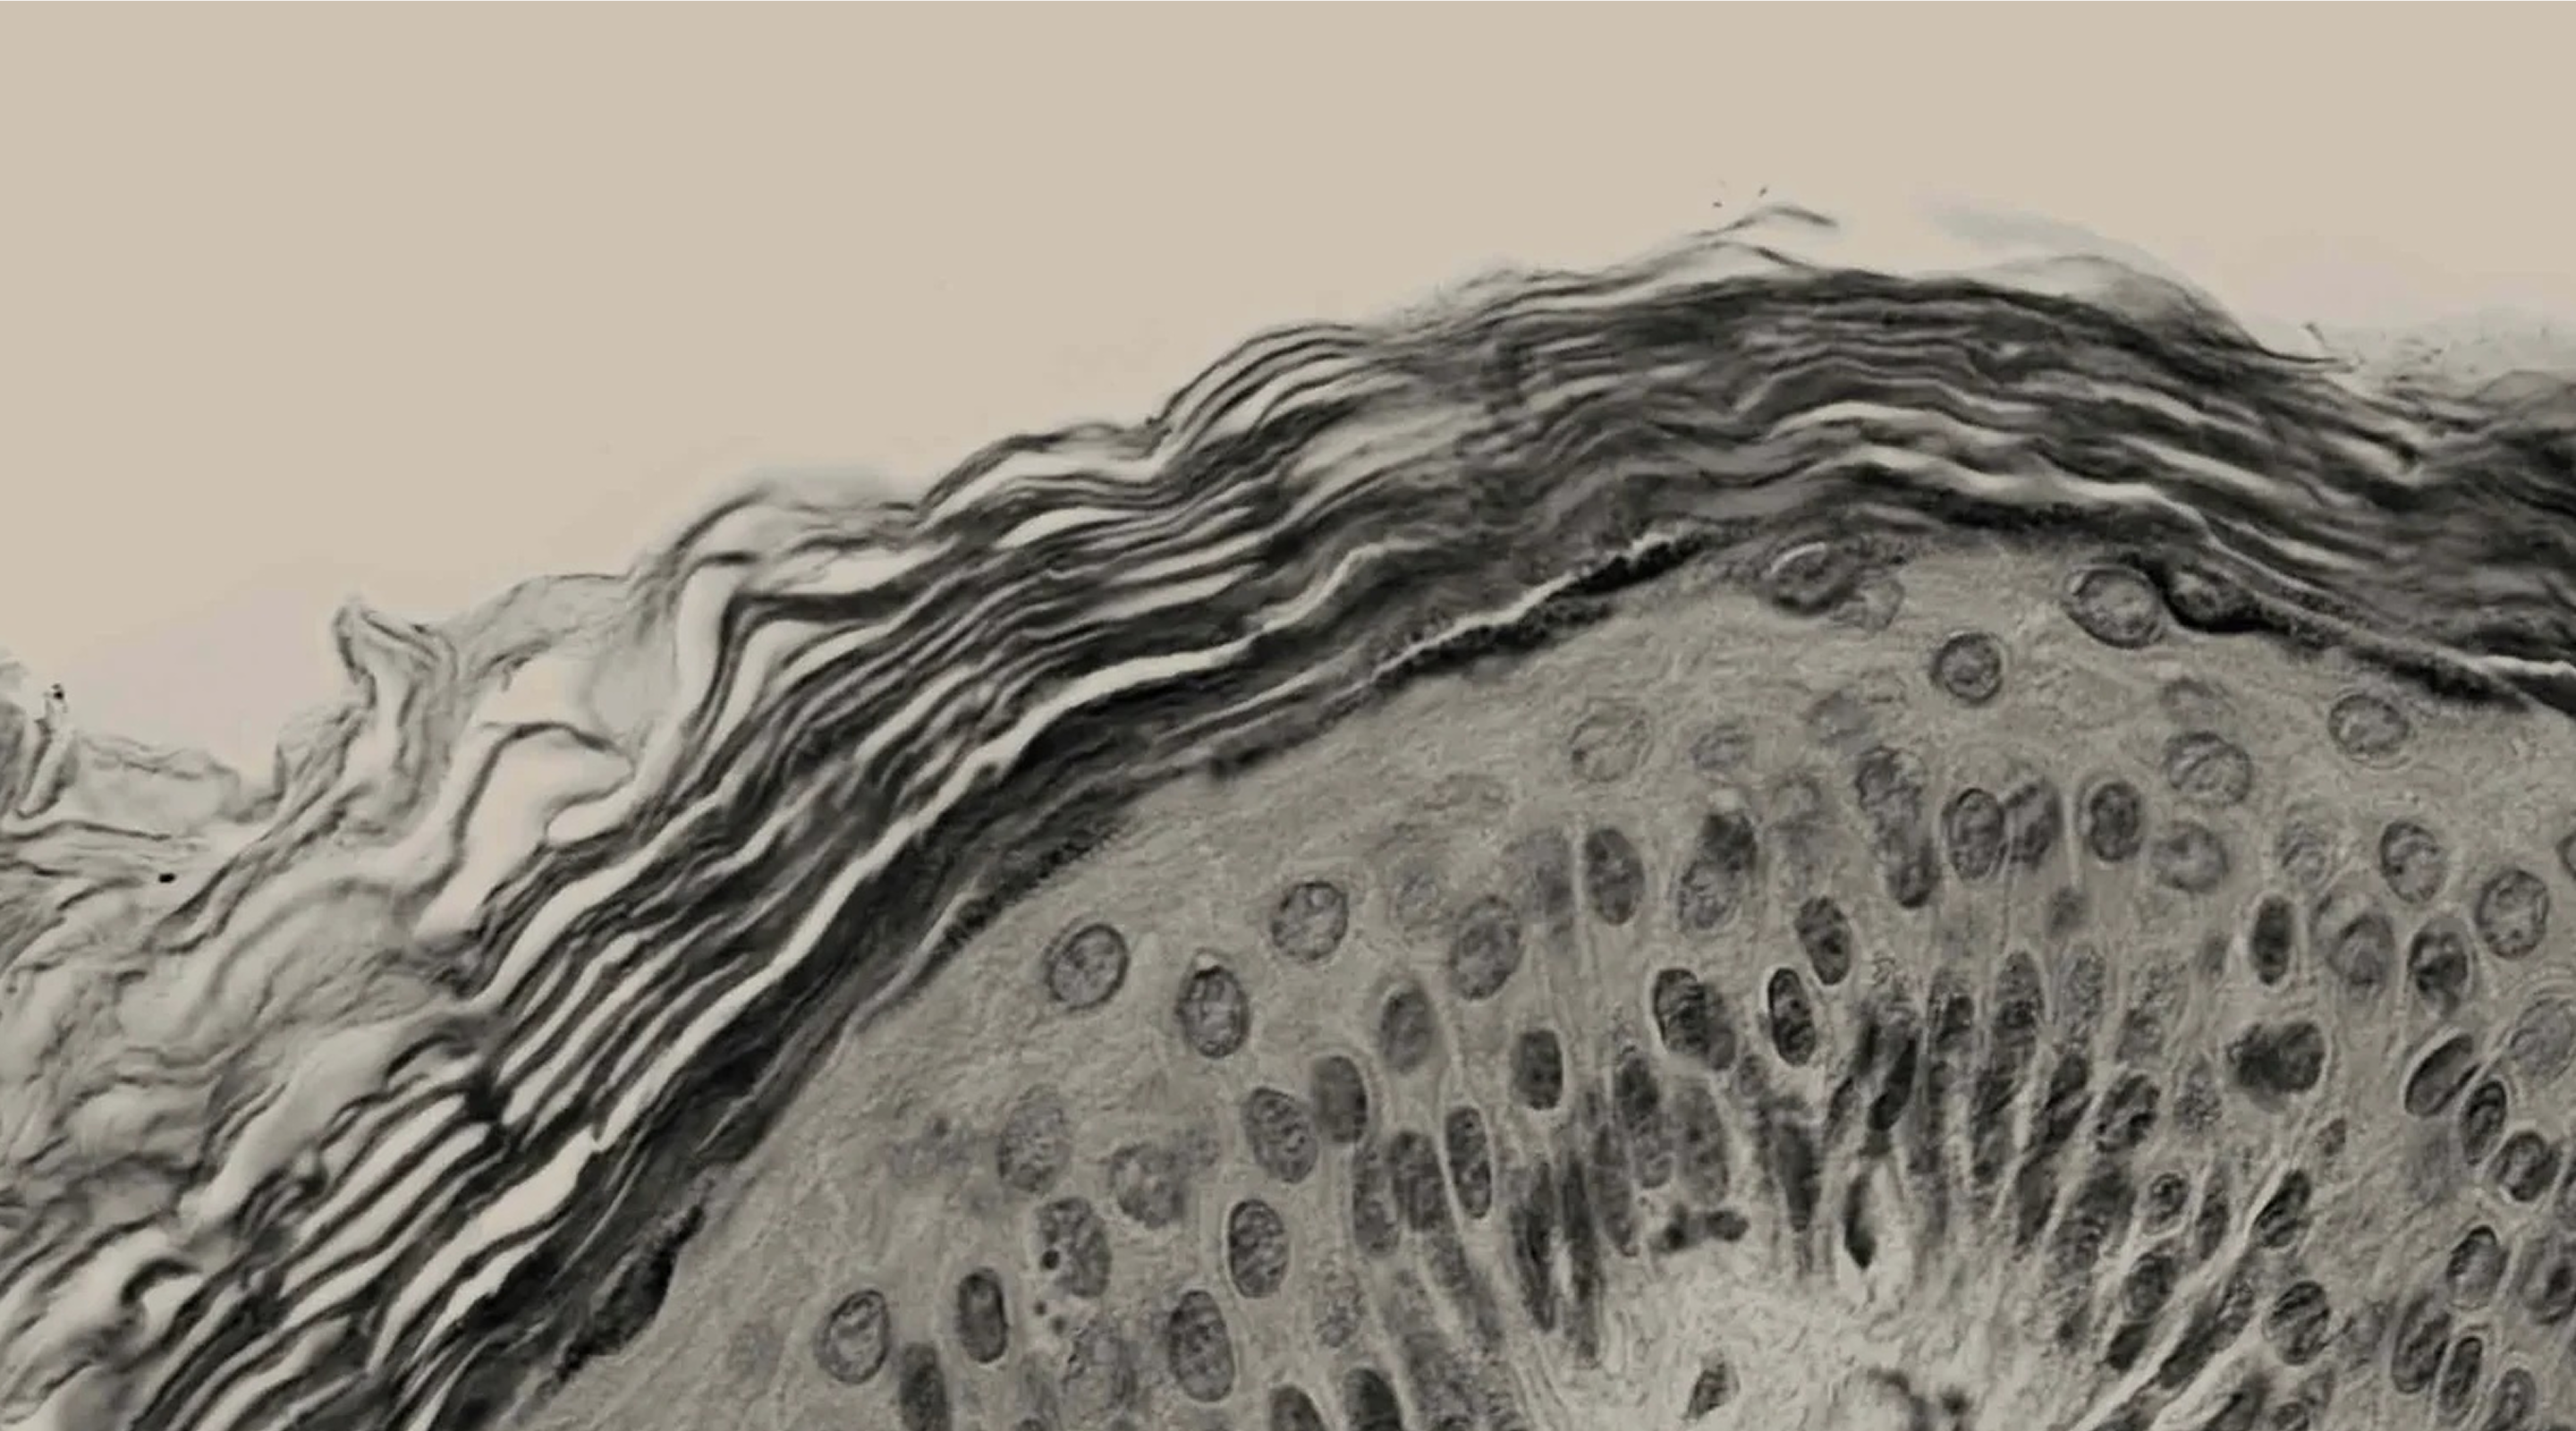

The skin has epidermal units that are responsible for melanin production and distribution, a process called melanogenesis. These units are composed of a melanocyte surrounded by keratinocytes and regulated by a closed paracrine system. Melanin is the primary determinant of skin, hair, and eye colour. And plays a critical role in photo protection due to its ability to absorb ultraviolet radiation (UVR).